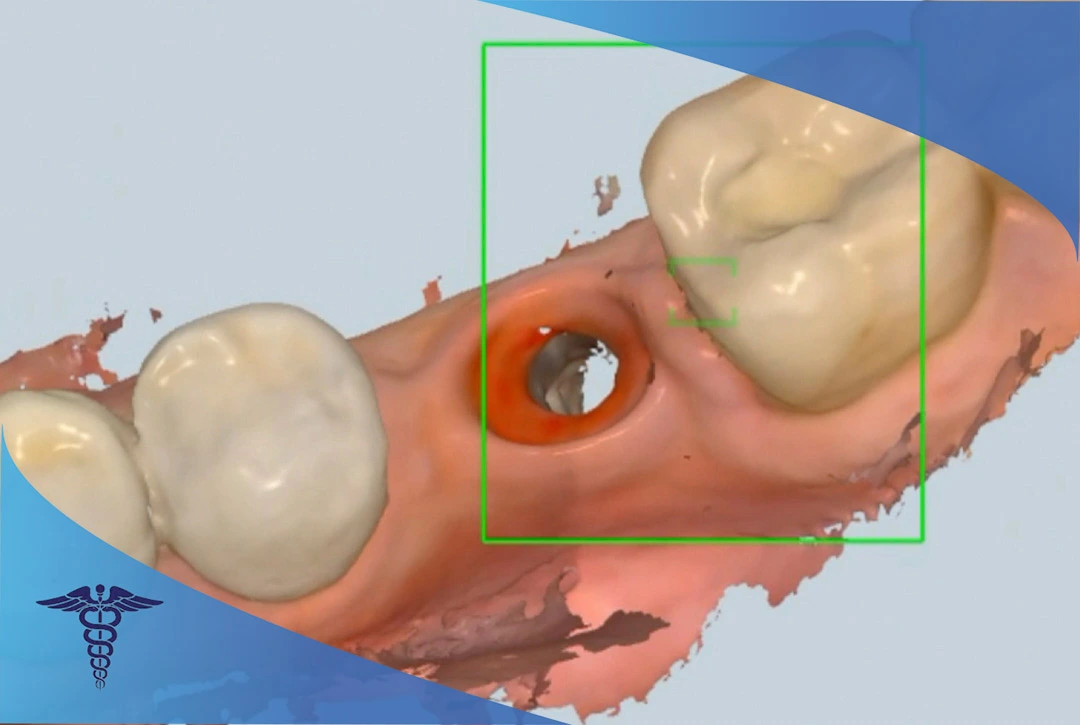

اولین گام مهم برای درمان ایمپلنت، ارزیابی کامل دندان های شماست. برای این کار عکس های سه بعدی با کمک اسکنر CBCT از داخل دهان گرفته می شود. این تصویر نشان می دهد که استخوان کافی برای قرار دادن ایمپلنت وجود دارد یا خیر. در صورتی که وجود نداشته باشد، باید درمان پیوند استخوان و حتی لیفت سینوس برای قوس بالایی را انجام داد تا فضای بیشتری برای دسترسی به استخوان وجود داشته باشد.

مرحله سوم: جراحی ایمپلنت 💉

در این مرحله دندانپزشک جراح هر گونه کارهای مقدماتی مورد نیاز از جمله پیوند استخوان، لیفت سینوس، کشیدن دندان و … را قبل از کاشت ایمپلنت دندان انجام می دهد. پس از اینکه جراحی لثه انجام و دوره بهبودی کامل شد، نوبت به کاشت ایمپلنت می رسد. برای هر قدم بی حسی دقیق در ناحیه لثه تزریق می شود تا امکان کاشت ایمپلنت وجود داشته باشد. پس از اتمام فرآیند کاشت ایمپلنت ممکن است دندانپزشک یک بریج مصنوعی موقت روی دندان شما قرار دهد تا در پایان دوره بهبودی و جوش خوردن ایمپلنت از آن استفاده کنید.

پس از جوش خوردن موفقیتآمیز ایمپلنتها به استخوان، ایمپلنتها باید با دندان از دست رفته شما جایگزین شود. با استفاده از اسکنر داخل دهانی سه بعدی، شکل دهان و پایه های ایمپلنت اسکن می شود. این اسکنهای دیجیتال به آزمایشگاه دندانپزشکی ارسال می شوند.